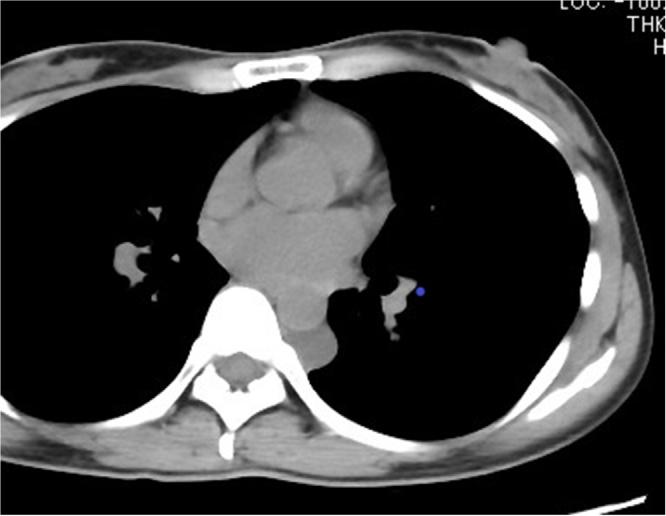

A 40-year-old woman was referred to our department for abnormal mediastinal tumor on computed tomography (CT). Chest CT revealed a 2-cm nodule in the left posterior mediastinum, while magnetic resonance imaging (MRI) T2-weighted scan revealed an elliptical, homogenous, and high-intensity neoplasm, and bronchogenic cyst or neurogenic tumor was suspected. She did not present with any symptoms. A thoracoscopic surgery was performed for the cyst removal. Histopathological examination revealed that the cyst wall was covered with a layer of columnar epithelium. Immunohistochemical staining revealed the presence of estrogen receptor (ER) and progesterone receptor (PgR). Therefore a diagnosis of mediastinal Müllerian cyst was made.

一名40岁女性因计算机断层扫描(CT)发现纵隔肿瘤异常转诊至我科。胸部CT显示左后纵隔有一个2厘米的结节,而磁共振成像(MRI)T2加权扫描显示为椭圆形、均匀、高强度的肿瘤,怀疑为支气管源性囊肿或神经源性肿瘤。她没有任何症状。为切除囊肿进行了胸腔镜手术。组织病理学检查显示囊肿壁覆盖有一层柱状上皮。免疫组织化学染色显示存在雌激素受体(ER)和孕激素受体(PgR)。因此诊断为纵隔苗勒管囊肿。